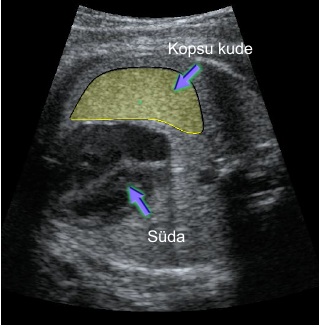

Ultrahelipildil kopsu analüüsimisele kuuluva pinna piiritlemine